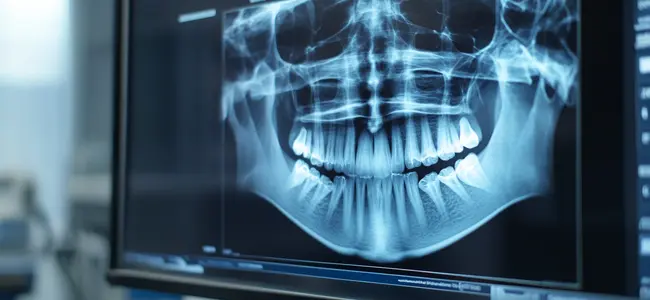

- Digital X-rays and imaging for precision diagnosis and effectiveness in treatment

Involves a focused examination and high-quality digital imaging to delineate the infection and help you formulate a personalized plan with upfront costs.